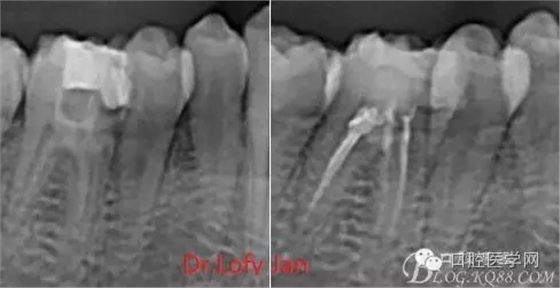

曲面斷層片在未試尖根管治療中的病例整理

前言:自己做的一些曲面斷層片在未試尖根管治療中的病例整理,發(fā)現(xiàn)問題很多包括自身的,技術(shù)的,還有設備的問題,予以總結(jié)整理并期待進一步提高。

病例分析:曲面斷層片在x線輔助診斷與檢查中目前大多數(shù)文獻和著作都建議只能作為初診拍片檢查手段,不能作為終末疾病的確診與手術(shù)療效的評價指標,臨床大部分中小型門診都因為設備不齊全導致信息偏差很大。